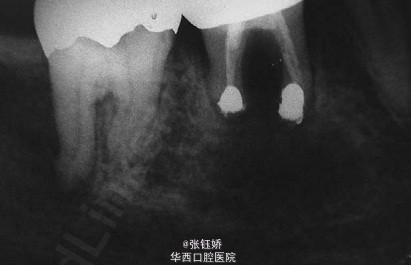

女,56岁,自觉左下磨牙区敏感不适,X线片示36牙已根充,远中根管超填,近中根管欠填,根管预备显示近中根管下段钙化,根尖周见较大暗影。考虑到患者牙合间距离很小不符合根尖手术适应症,故拟行意向性牙再植术。